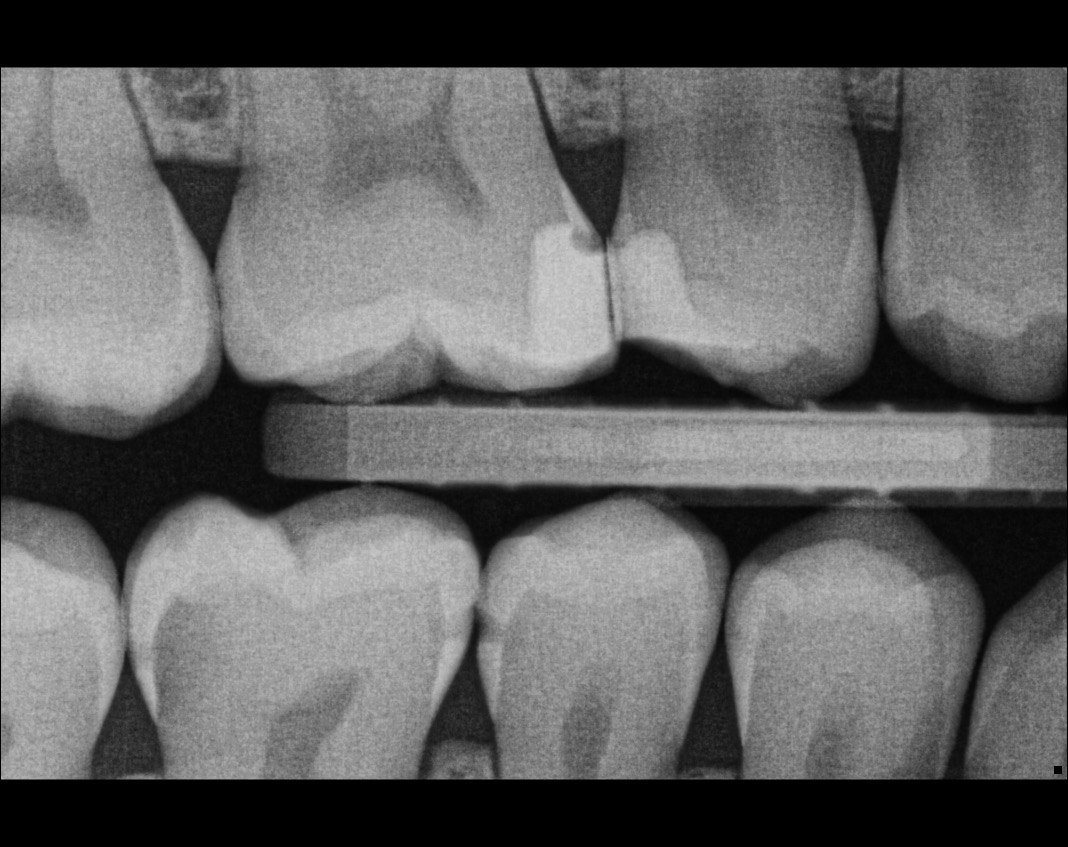

Question 4: what is the condition of the distal of the tooth # 4.1 and mesial of the tooth #3.1 respectively?

Question 17: What are the caries extention in distal of the tooth # 2.4 and mesial surface of the tooth # 2.5 respectively?

Question 18: What is the option that can describe the distal surface of the tooth # 1.7?

Question 19: What is the option that can describe the mesial surface of the tooth # 1.8?

Question 20: What is the option that can describe the distal surface of the tooth # 4.5?

Question 21: What options can describe the mesial and distal surfaces of the tooth # 4.7 respectively?

Question 22: What codition cannot be seen in the lower teeth in this X ray?

Question 23: What option can describe the distal surface of the tooth # 4.5?

Question 24: Which condition can be detected in the following X ray?

Question 25: What treatment is appropriate for distal surface of the tooth # 3.4 and mesial surface of the tooth # 3.5?